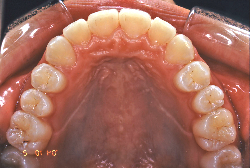

叢生(そうせい)

凸凹な歯並びのことを叢生といいます。矯正歯科に来院する患者様の主訴の中で、最も多いのが「配列の凸凹を真っ直ぐにしたい」というものです。歯の大きさと顎の大きさの調和がとれていないことが原因です。

凸凹を主体としたケースの場合、当院の平均治療期間は18ヶ月ですので、このケースは少し長めに経過しました。理由の一つは凸凹の程度がかなり重症だったと言うことですが、もう一つは、右下第2大臼歯が45度くらい前傾していたため、それを整直化させるために時間を要したと考えています。いずれにしても最終結果は大変よい状態と思います。

治療前は並びが乱れて見た目が悪いというのはもちろん問題ですが、歯科医学的に一番困るのは噛み合わせが悪いという点です。上下の犬歯(3番目の歯)は、上下的に離れた位置にあるため接触することができません。つまり歯としては存在していても、歯としては機能していないということです。